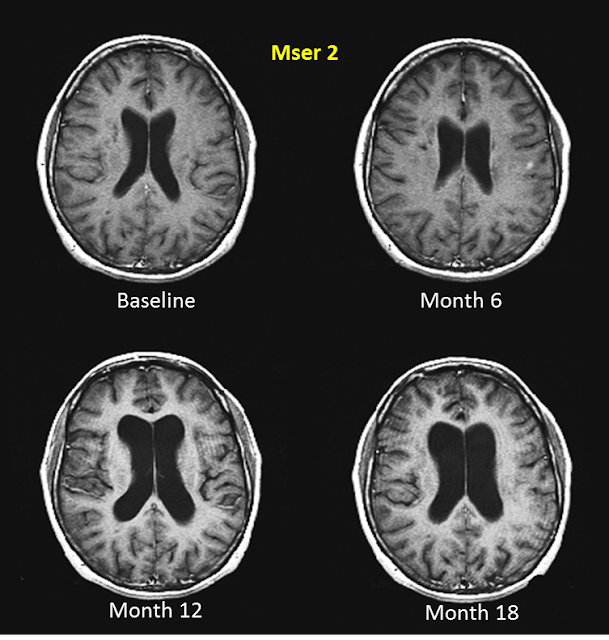

"The sets of MRI studies below are from two MSers with RRMS who were followed for 18 months; please note the degree of brain atrophy that occurred during this period of time? A picture is worth a thousands words and these images tell you how damaging MS can be to the brain."